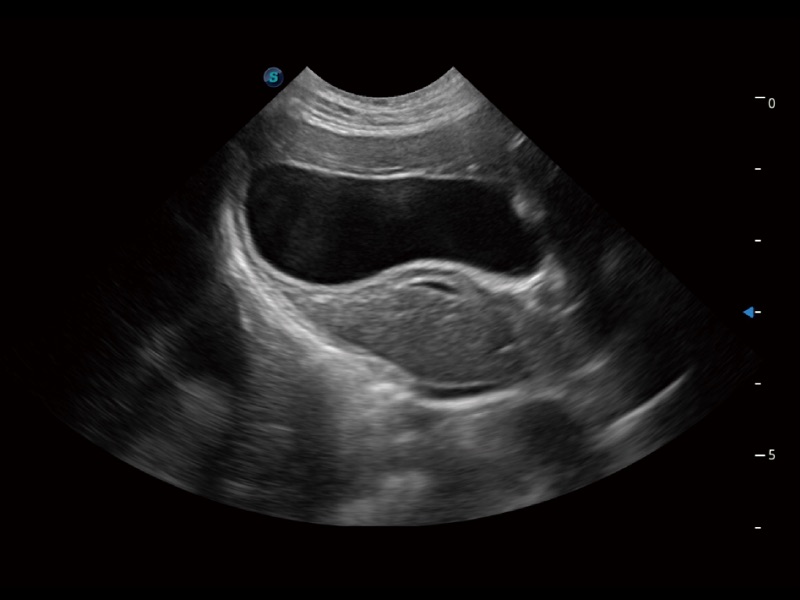

动物是人类最亲密的朋友和最值得信赖的伙伴。乐玩lewin国际也一直致力于探索动物专用的超声影像解决方案。全新推出的ProPet系列,是乐玩lewin国际在动物超声影像智能化、专业化、精准化的一次跨越式革新。动物不能用言语来表述自己的不适,通过超声影像,ProPet系列搭建了动物医生与不同物种沟通的“桥梁”,为动物医生注入了“治愈之力”。 ProPet 70将是您值得信赖的超声伙伴。它配备了复合材料线阵探头,帮助动物医生获得卓越精准的临床图像。同时ProPet 70直观便捷的操作体验以及专业的测量工具,可为不同体型和生理结构的动物带来全面临床评估,切实为动物医生提供智能、专业、精准的超声影像解决方案。

ProPet 70 进一步提升了微米成像算法,更加注重对基础原始图像的还原和保留,在有效减少斑点噪声、增强组织边界显示的同时,避免过度优化丟失真实的解剖信息。

ProPet 70专为动物医生设计,对不同的动物体型和生理结构作出了针对性的优化。通过动物影像专用软件,可满足个性化的应用需求,帮助动物医生获得更精确的诊断数据。

ProPet 70 全新的动物超声智能软件和丰富的探头群,为动物医生提供了高清晰度和精细分辨率的图像,无论在宠物、马科、畜牧还是实验室动物等应用中都可以轻松应对,为您的日常工作带来满意的体验。